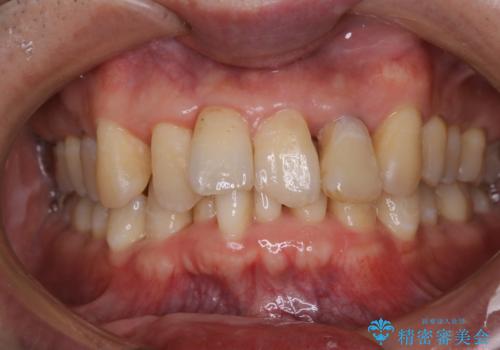

歯周病の治療前にまずはモチベーションUPにPMTCでステインの除去

- 今後、歯周病の治療を行う予定のため、まずはステインなどの除去を希望されました。PMTC60分コースを行いました。

PMTCを行うことにより、スッキリと爽快感が得られたり、見た目も清潔感のある状態になるため、今後の治療などに対するモチベーションUPにも繋がります。